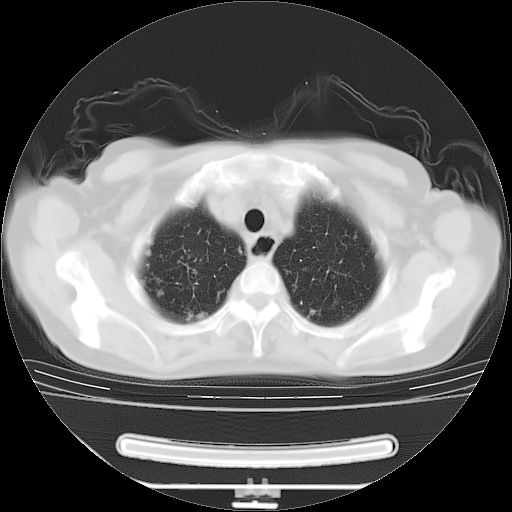

患者女性,72岁,慢性咳嗽3月余,曾抗炎治疗无效果,最近抗结核治疗约半月余,症状缓解。

ct示两肺粟粒状病灶,以两肺上叶尖后段及下叶背段分布为主;首先考虑结核。请战友们分析。

考虑 1 弥漫性泛细支气管炎, 2 结核不除外/.  有小叶中心结节 和 树芽征!!

两肺内病灶呈小结节状和树芽状,纵膈的肿大的淋巴结密度不均匀,并见有钙化,考虑为两肺结核可能更大些。

两肺内病灶呈小结节状和树芽状,纵膈的肿大的淋巴结密度不均匀,并见有钙化,多形态病灶,考虑为两肺结核,肝内考虑小囊肿。

病灶以结节为主,大部分边界清楚,分布不均,病灶形态较单一,偶见空泡征,纵膈淋巴结肿大钙化,无结核中毒症状考虑 感染性病变【真菌类可能性大】,细支气管肺泡癌。其他待排

片子很好,质量很高,两侧肺门淋巴结肿大并有钙化,两肺弥漫病灶,首先考虑tb并播散,但年龄大了呀(72岁)小细胞肺癌不能除外,如果是肺癌也没什么大的治疗了,建议正规抗结核治疗后复查